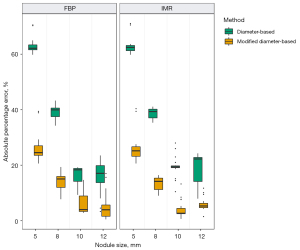

In the LSCT001 series of scans, in which 10-mm nodules were scanned and measured under six different settings, the APE was significantly less with the modified diameter-based volume calculation than with the diameter-based volume calculation (Wilcoxon signed-rank test, P<0.05) under each scan setting (Figure 4 and Table 1). In the Lungman series of scans, in which 5-, 8-, 10-, and 12-mm nodules were scanned with different reconstruction algorithms, the APE was significantly less with the modified diameter-based calculation than with the diameter-based calculation for all nodule sizes (Wilcoxon signed-rank test, P<0.001) and each reconstruction algorithm (Figure 5 and Table 2). The APE median increased as the size of the nodule decreased. This trend was statistically significant (Jonckheere-Terpstra test, P<0.001), regardless of the reconstruction algorithm (FBP and IMR) and volume measurement method (diameter-based and modified diameter-based volume calculations).

The inter-scan variability for the volume is as much as ±25% (13,14); accordingly, 25% has been used in some screening studies as the minimal percentage volume change signifying true growth (3,4,15). In our study, the APE of the diameter-based volume relative to the voxel-counting volume was substantial, and increased as the nodule size decreased, with medians exceeding 25% for 5- and 8-mm nodules. Our phantom study results may be applied to clinical settings. Unless consistent volume measurement method is used, follow-up images of small nodules can be prone to false interpretation: nodule growth or shrinkage. To minimize those confusing interpretations and avoid inconsistent nodule management, an adequate conversion should be applied when comparing diameter-based and voxel-based volumes of a pulmonary nodule. Among several factors that can cause disparity between two volume assessments, we focused on the loss of at least one pixel spacing when measuring the physical distance between two voxels, and added one extra pixel spacing to the diameter in each axis during the volume calculation. As a result, this simple new method significantly reduced the APE to a median of around 25% for 5- and 8-mm nodules, which would provide more consistent nodule management.